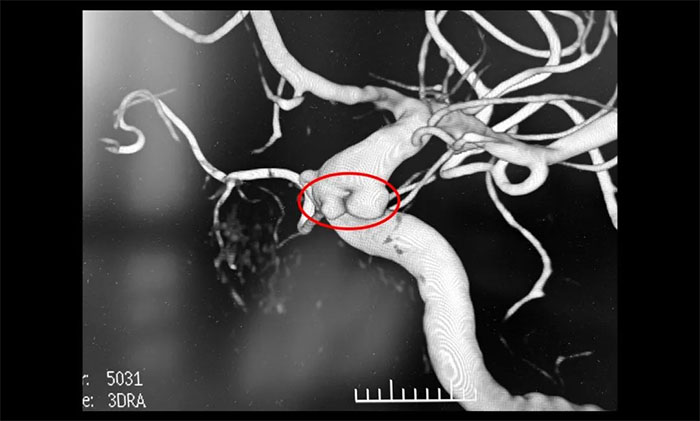

患者為59歲女性。因近期出現(xiàn)頭暈、頭痛伴視物模糊入院就診,行磁共振檢查發(fā)現(xiàn)右側(cè)頸內(nèi)動脈C6段可疑小突起,考慮腦動脈瘤。行腦血管造影提示,右頸內(nèi)動脈眼動脈段多發(fā)動脈瘤。

▲ DSA提示,右頸內(nèi)動脈眼動脈段多發(fā)動脈瘤

席剛明教授分析認為,該動脈瘤不規(guī)則,破裂風(fēng)險大,建議積極治療。但該動脈瘤位置不適合顯微手術(shù)夾閉治療,而常規(guī)支架輔助栓塞難以實現(xiàn)眼動脈起始部動脈瘤栓塞,后期動脈瘤進展及復(fù)發(fā)風(fēng)險高,較好的治療方式為血流導(dǎo)向裝置置入。大家一致同意治療方案,與家屬詳細解釋溝通后,同意進行血流導(dǎo)向裝置置入治療。